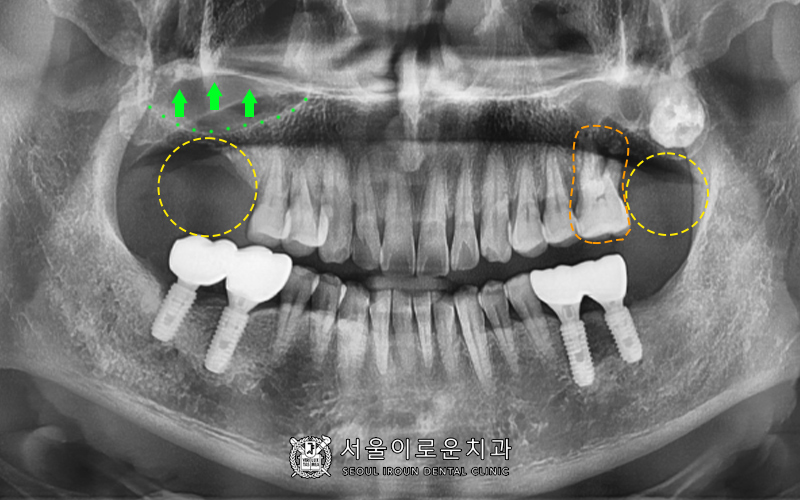

환.자분의 경우

위에 큰 어금니 4개 중

3개는 상실되어있고

1개는 상태가 좋지않아

큰 어금니의 기능을 하는 치아가 없어

재건이 필요한 상황이었습니다.

왼쪽 위 어금니(#26) PA 사진입니다.

유일하게 남아있는 큰어금니 (#26)의

상태를 보시면,

1)심한 치주염으로 (→잇몸뼈 소실)

2)2️⃣이상의 동요도(++)와

3) 씹을 때 통증이 있으신 상태로

발치가 필요했습니다.😭